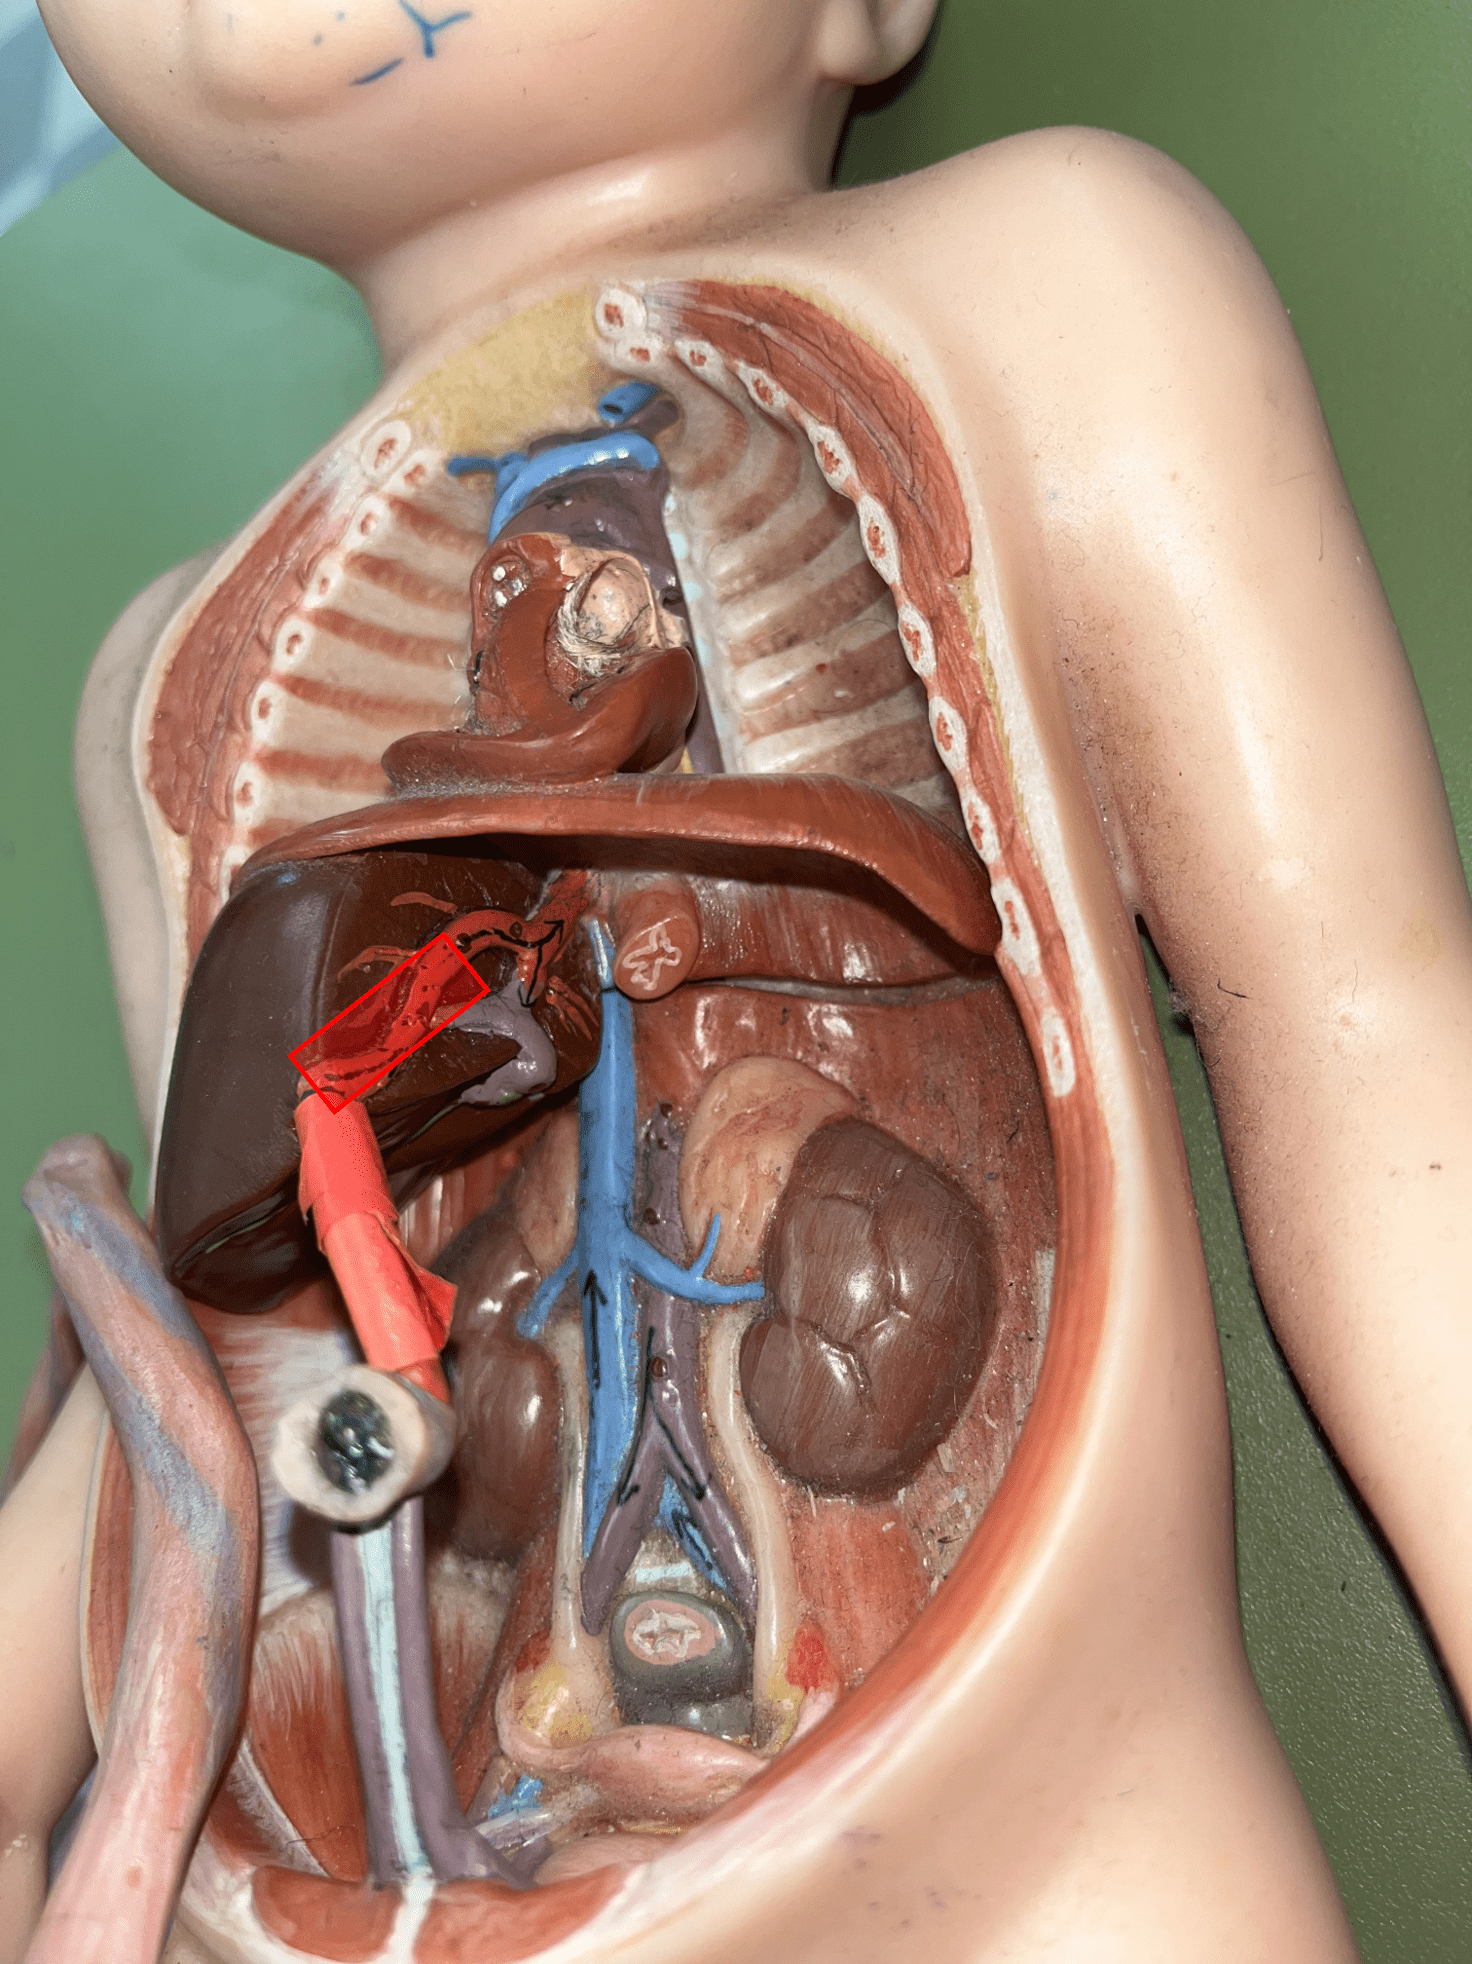

tunica externa

• Also known as the tunica adventitia.

• Composed of loose connective tissue and collagen fibers.

7

New cards

8

New cards

tunica media

• The smooth muscle allows for vasoconstriction and vasodilation.

• A thin layer of elastic connective tissue.